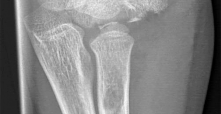

A 3-year-old girl presents with progressive bilateral genu varum. Radiographs reveal a prominent medial metaphyseal beak and a sharp diaphyseal-metaphyseal angle. Which of the following is the most accurate statement regarding the suspected underlying pathology?

Explanation